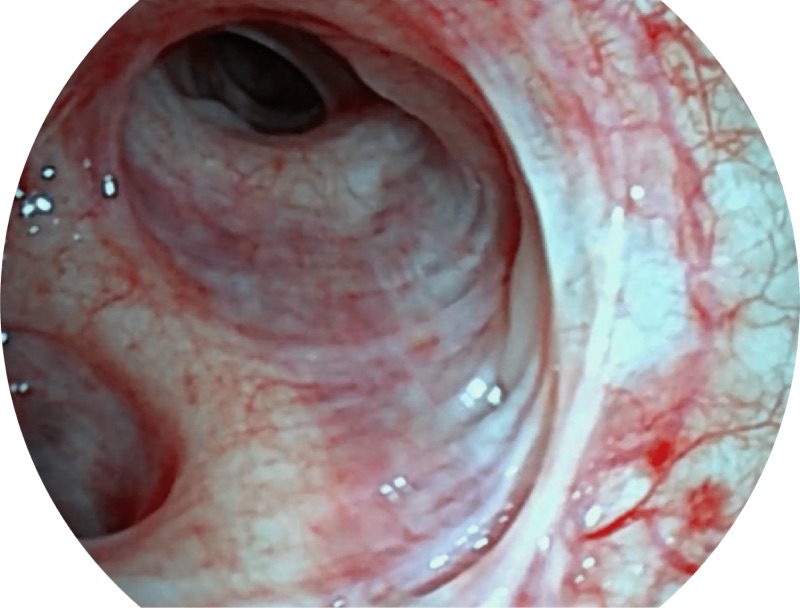

• 高清画质

帮助医生更加清晰地观察气管表面病灶

• 更细外径

EB-5H20具有4.9mm外径及2.0mm钳道提升对外围支气管检查能力